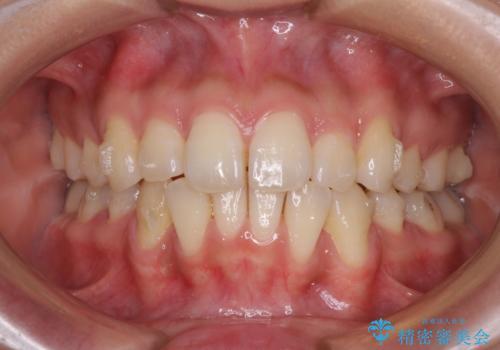

- 以前の矯正治療の後戻りにより、上下の前歯がでこぼこになってしまったことを気にして来院された患者様です。

口元がこれ以上突出することなく前歯の叢生が改善できるよう、歯と歯の間を削ってスペースを獲得し、インビザラインを用いて整えていくこととしました。

目安の装着時間である1日22時間をしっかりと実践してくださり、半年強という短期間で治療を終えることができました。